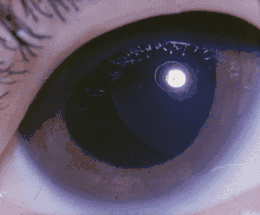

| A six-year-old female with Weill-Marchesani syndrome, which has caused a dislocated lens. | |

The eye manifestations typically include unusually small, round lenses of the eyes (spherophakia), which may be prone to dislocating (ectopia lentis), as well as other ocular defects. Due to such abnormalities, affected individuals may have varying degrees of visual impairment, ranging from nearsightedness myopia to blindness. Researchers suggest that Weill–Marchesani syndrome may have autosomal recessive or autosomal dominant inheritance.[1]